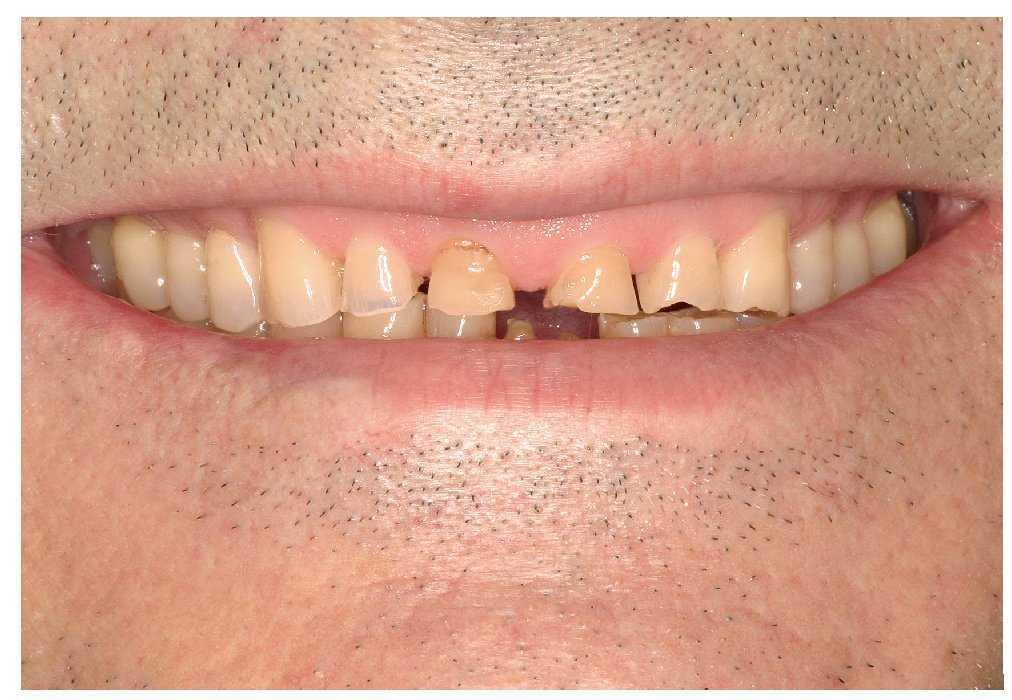

Un paciente de 64 años de edad acudió a la Policlínica Universitaria de Prostodoncia remitido por su odontólogo de cabecera para la rehabilitación protésica de su dentición, que presentaba evidentes muestras de desgaste. La anamnesis general no aportó datos reseñables salvo un diagnóstico de hipertensión. En la anamnesis específica se puso de manifiesto que durante la noche el paciente presentaba rechinamiento y apretamiento dentarios. En la exploración funcional no se observaron molestias musculares ni en las ATM. Sólo se constató un chasquido alternante y ocasional en las articulaciones temporomandibulares. La exploración extraoral reveló una musculatura masticatoria hipertrófica. El paciente presentaba una línea de sonrisa alta, también denominada línea de sonrisa gingival55 (figs. 1 y 2).

La exploración intraoral arrojó los siguientes resultados:

Ausencia de los dientes 18, 28 y 38

Déficit generalizado de tejidos duros dentarios por atrición, abrasión y erosión

Destrucción de los tejidos duros dentarios más acusada en el sector anterior de ambas arcadas (fig. 3)

Figura 3. Destrucción grave de los tejidos dentales duros.

Mordida borde a borde